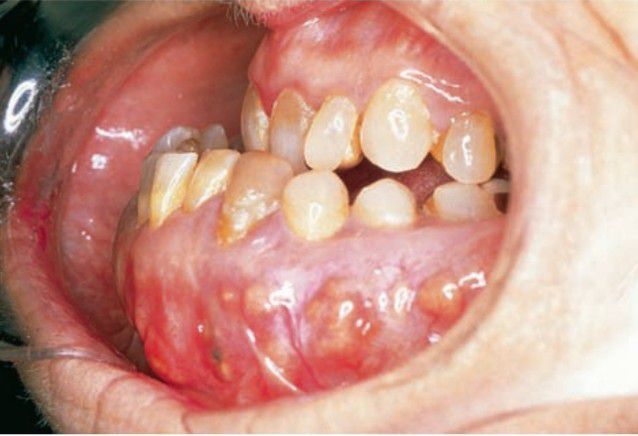

Paget's disease of mandible

Patients develop pain, deafness, blindness, and headache caused by bone changes; initial complaint may be an ill-fitting denture.